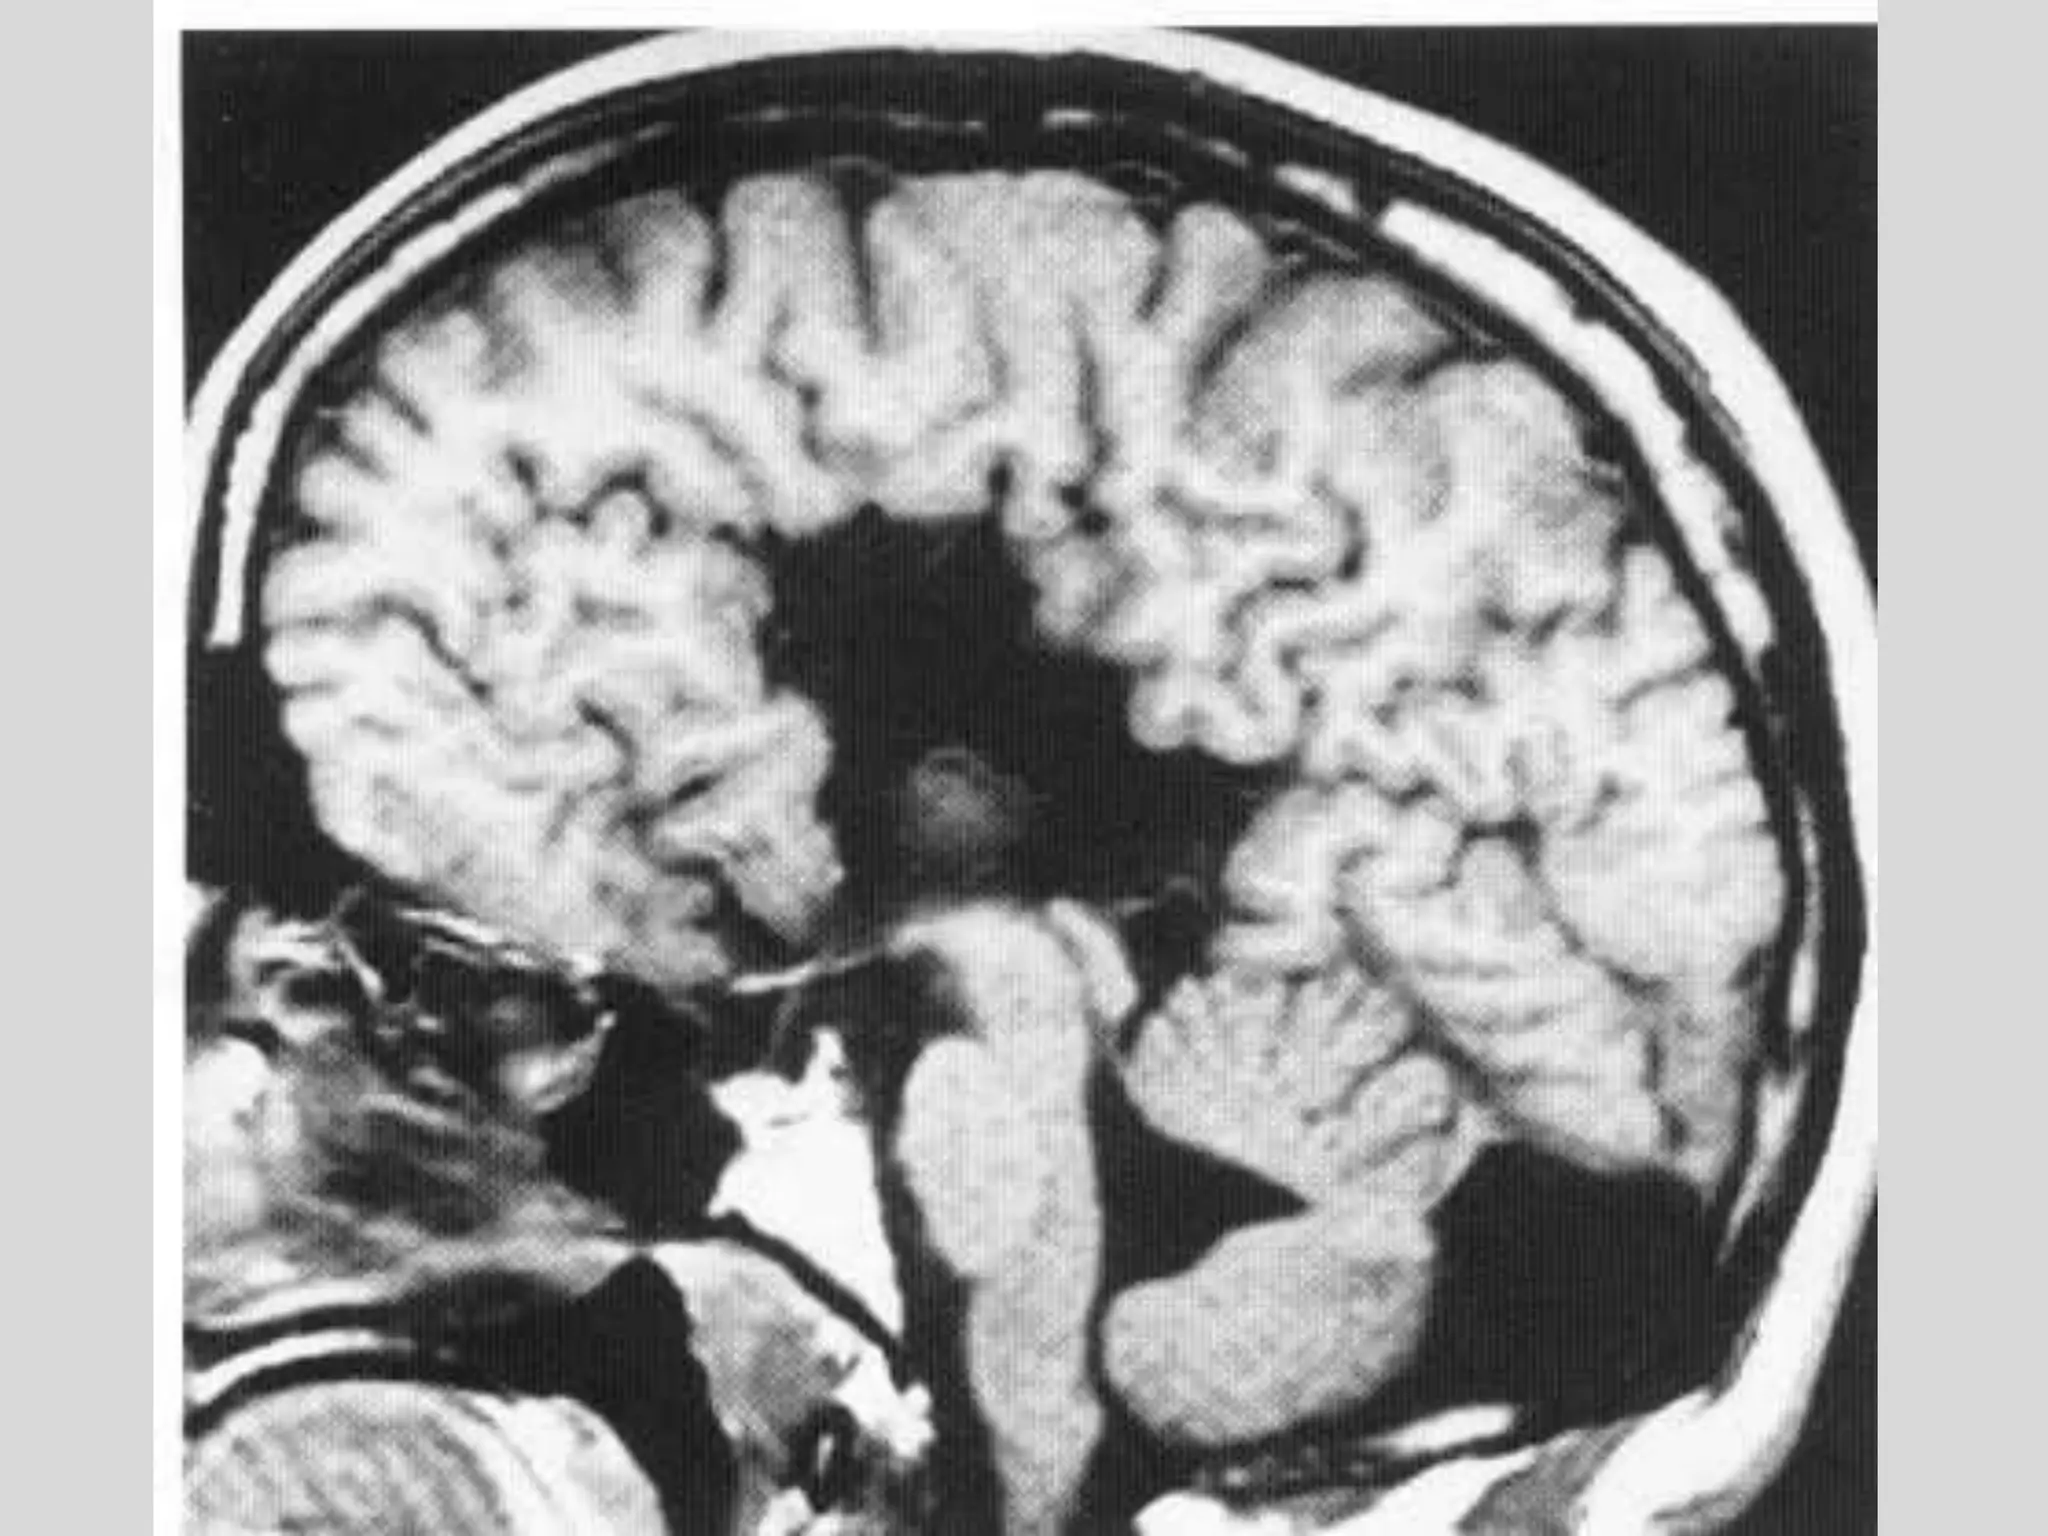

Normal MRI

MR-T1 MR-T2 xray-CT

Normal tissue

dense bone Dark Dark Bright

Air Dark Dark Dark

Fat Bright Bright Dark

Water Dark Bright Dark

Brain anatomical interm. interm.

MR-T1 MR-T2 CT

enhance

ment

Abnormal tissue

infarct dark bright Dark subacute

bleed Bright bright Bright no

tumor Dark bright dark Yes

MS plaque Dark Bright dark acute